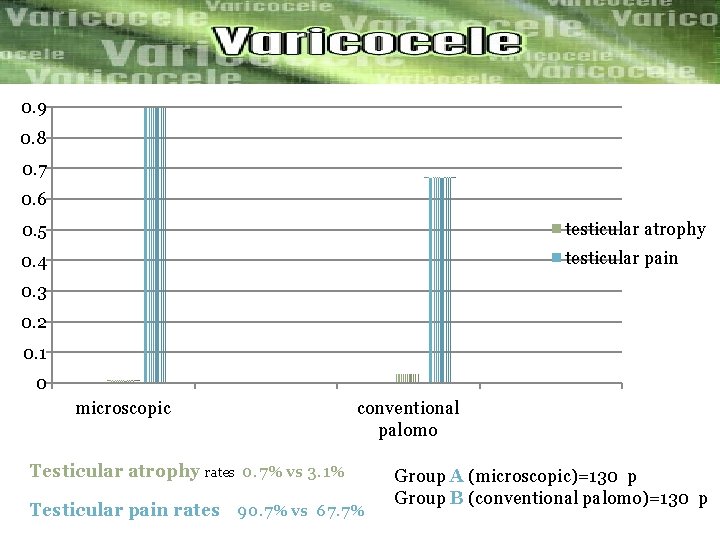

Objective: to evaluate the post operative complications Of microscopic and conventional palomo varicocelectomy Microscopic palomo varicocelectomy Group A(n=130) Conventional palomo Group B (N=130) The Postoperative complications and recurrence were compered Between the tow groups. The result after 1 year of follow up were…………. .

0. 9 0. 8 0. 7 0. 6 0. 5 testicular atrophy 0. 4 testicular pain 0. 3 0. 2 0. 1 0 microscopic conventional palomo Testicular atrophy rates 0. 7% vs 3. 1% Testicular pain rates 90. 7% vs 67. 7% Group A (microscopic)=130 p Group B (conventional palomo)=130 p

Recurrence rates 0. 06 0. 05 0. 04 0. 03 recurrence 0. 02 0. 01 0 microscopic Recurrence rates Group A 5. 3% vs Group B 3. 8% conventional palomo